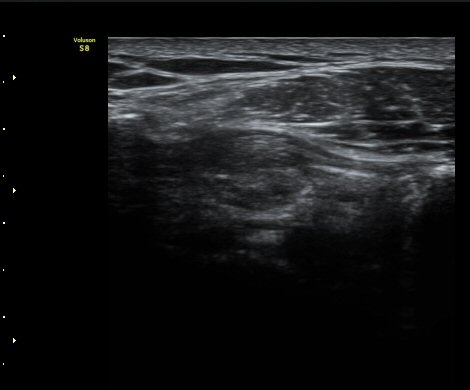

Áõ·Ê 2)

°ßºÀ¿À±¸µ¹±âÀδë Á¾´Ü¸é°Ë»ç¿¡¼­ ÀδëÀÇ ¿ÜÃø¿¡ ±¹¼ÒÀûÀÎ ÀÎ?ºñÈİ¡ °üÂûµÈ´Ù(»çÁø 3).

±Ø»ó°Ç Á¾´Ü¸é°Ë»ç½Ã ±Ø»ó°ÇÀÇ Ç¥Ãþ¿¡¼­ °üÂûµÇ´Â °ßºÀ¿À±¸µ¹±â Ⱦ´Ü¸é°Ë»ç»ó¿¡¼­

ÀδëÀÇ ºñÈİ¡ °üÂûµÈ´Ù(»çÁø 4). ±Ø»ê°ÇÀÇ Á¾´Ü¸é°Ë»ç¿Í Ⱦ´Ü¸é°Ë»ç¿¡¼­ ±Ø»ê°Ç ½ÉÃþ¿¡

Àú¿¡ÄÚ º´º¯ÀÌ °üÂûµÈ´Ù(»çÁø 5, 6).